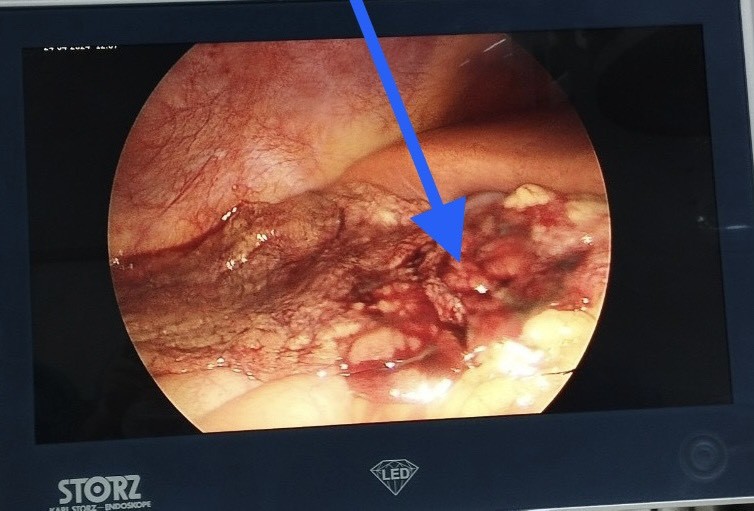

Hình 4,5: Hình ảnh xoắn + hoại tử mạc nối lớn trong mổ nội soi